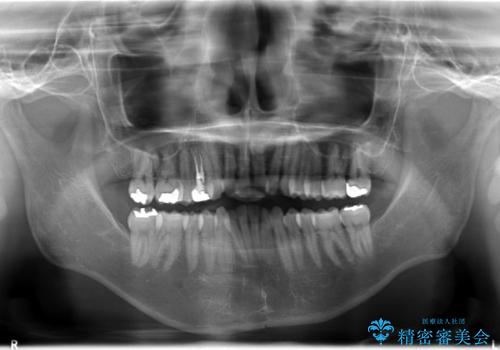

フルリンガル矯正 非抜歯でガタつきを整える

- フルリンガルワイヤーによる非抜歯治療を計画しました。

フルリンガルは違和感も強く操作も煩雑になるため、あまりおすすめはしていませんが、お仕事の都合などでどうしても装置を付けられない&マウスピースを管理することができない、場合はやむなく選択することもあります。